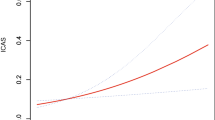

Power analyses were performed post hoc to evaluate the smallest detectable effect size in the cohort. The smallest detectable OR for SVD as a binary outcome (present vs absent) was calculated based on minor allele frequency, the proportion of SVD cases, and the number of participants using the R genpwr package version 1.0.4 [28]. A significance level α = 0.05 was chosen for the analysis. All analyses were performed with R version 4.0.0.

Figure 1 illustrates genotype frequencies and minor allele frequencies for participants with versus without SVD. When analysing genotype frequencies by presence versus absence of SVD with the chi-square test, the difference in genotype frequencies was not statistically significant (p = 0.758). Likewise, minor allele frequencies by presence versus absence of SVD did not differ between the groups (p = 0.553). Also, when analysing the additive effect of the Hp1 alleles by simple logistic regression, we did not detect a significant association between SVD and the number of Hp1 alleles (OR 1.14 95% CI 0.73–1.75, p = 0.566).

A limitation of this study is that the statistical power does not allow us to reject the possibility of a subtle association between Hp-genotype and SVD. However, to the best of our knowledge, this is the largest study with brain-MRI and Hp genotyping in type 1 diabetes to date. Our statistical power analysis showed that effect sizes of OR 1.91 or larger would be detectable with 80% probability (α = 0.05) for this number of participants, indicating that the study is well-powered to detect more prominent associations. Of note is, that although we would have been able to detect larger effects (OR > 1.91), the sample size required to detect more subtle effects (OR < 1.5) with a probability of 0.8 is 4,295 participants (α = 0.05). Regardless, we consider the standardised brain MRI and the detailed assessment of the images to be a substantial strength of our study. Another strength of our study is the unique and well-characterized study population.